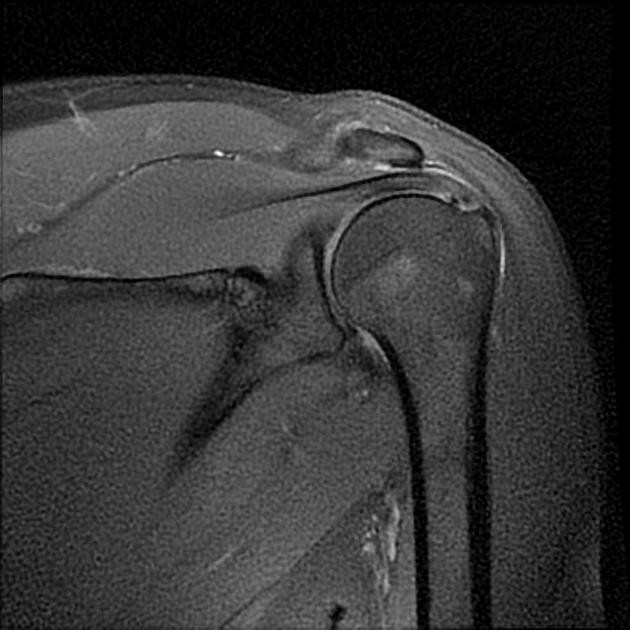

- MRI

- MR arthrogram

1. SLAP Tear (Superior Labrum Tear)

A SLAP tear affects the top part of the labrum where the biceps tendon attaches.